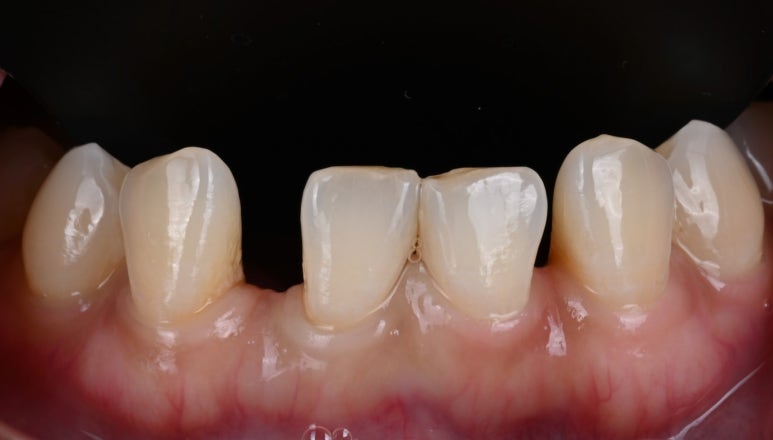

26.03.19

빈 공간의 크기가 제각각이었기에,

각 부위에 맞는 맞춤형 복합 치료를 계획했습니다.

1) 좁은 공간은 레진으로 (바이오클리어)

상대적으로 공간이 좁은 곳은

치아를 전혀 깎지 않는

바이오클리어 레진 수복을 통해

자연스럽게 공간을 메웠습니다.

26.03.19 레진 치료를 위한 러버댐 장착

26.03.19 바이오클리어를 이용한 레진 수복